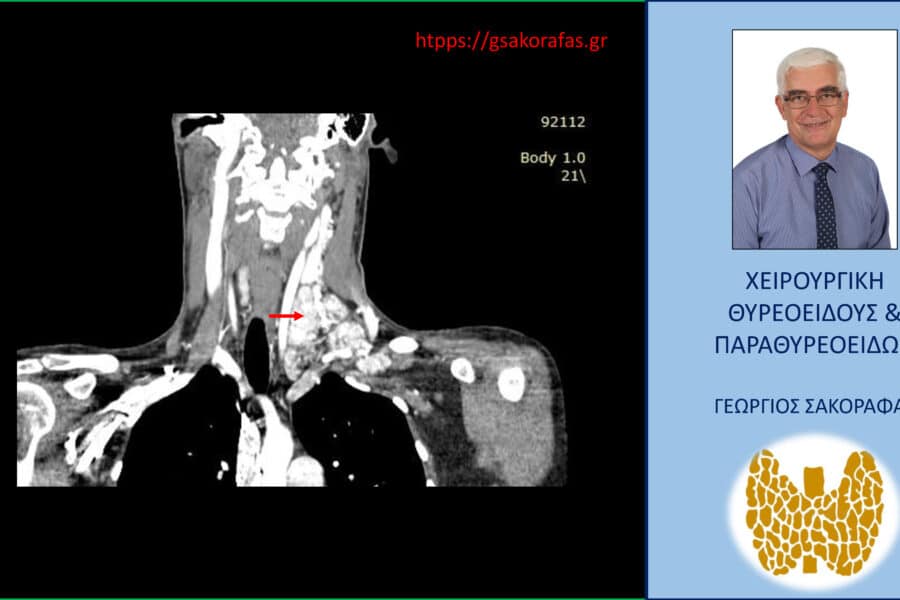

Καρκίνος ΘυρεοειδούςΘηλώδης Καρκίνος Θυρεοειδούς Επιθετικός καρκίνος θυρεοειδούς σε νεαρό ασθενή μας με προεγχειρητική διάγνωση παραπομπής «βρογχοκήλη» Επιθετικός καρκίνος θυρεοειδούς σε νεαρό ασθενή μας με προεγχειρητική διάγνωση παραπομπής «βρογχοκήλη» Παρουσίαση περιστατικού…George Sakorafas28 Μαρτίου 2026